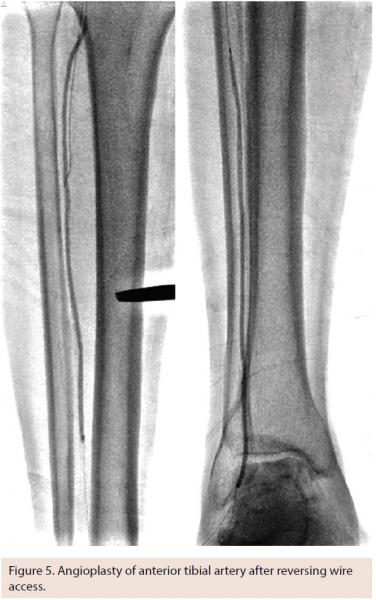

Tibio-pedal artery access (TPAA) is being used with increasing frequency as alternative access to facilitate procedural success in LEAI. This technique is usually employed in the setting of CLI and tibial artery intervention, but may offer potential practical advantages for popliteal artery and even superficial femoral artery (SFA) intervention in unique situations. While others have described TPAA access for intervention for claudication, we have not found it to be necessary in patients with claudication and primarily femoropopliteal disease. In our practice, TPAA is only used in the setting of CLI and in only 5%-10% of those patients. That said, our threshold for moving to an alternative access site with failed antegrade recanalization in tibial arteries has been lowered.

Equally as important to vessel access is an exit strategy that avoids local complications. Acute occlusion, thrombosis, or dissection can be a devastating outcome after a complex tibial intervention. Manual pressure is most commonly used at the level of the foot; however, prolonged balloon inflation is also very commonly used if any kind of wire-reversal technique has been employed. This is the standard approach in our practice.